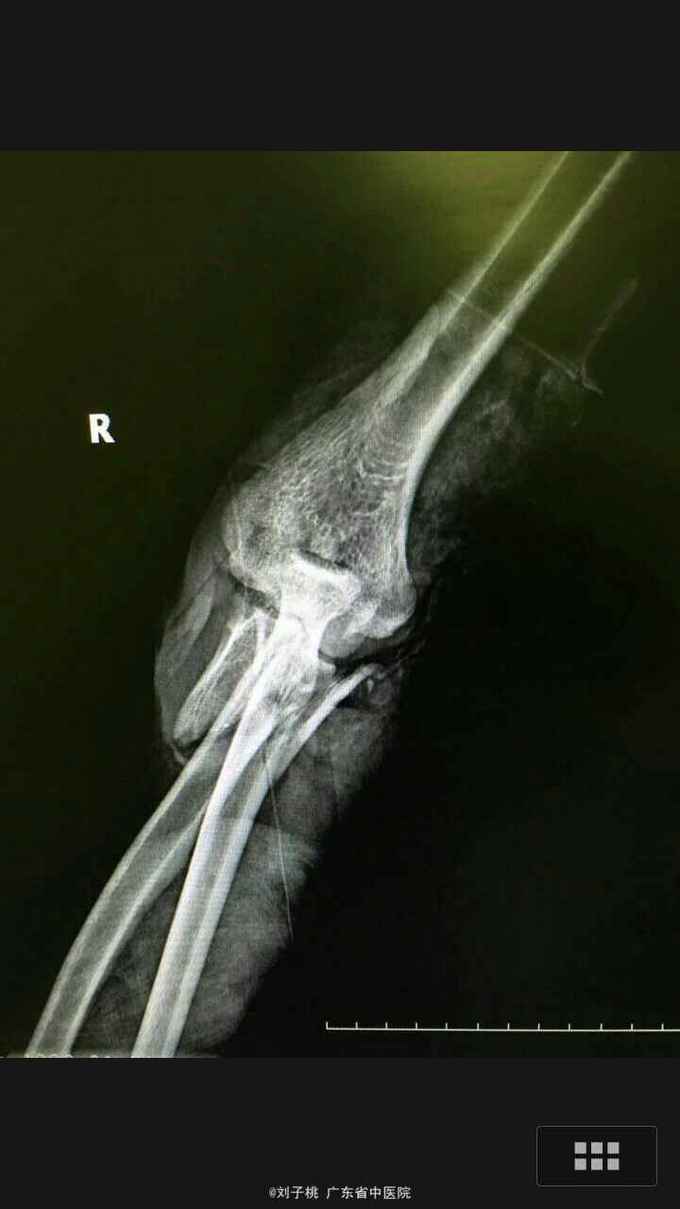

#骨科科室play#右肘开放性孟氏骨折

骨折 尺神经断裂 孟氏骨折

25岁男性,刀砍伤右肘致疼痛畸形入院。既往体健,无过敏史。

右肘开放性孟氏骨折,尺神经断裂,急诊行清创内固定加神经修复。